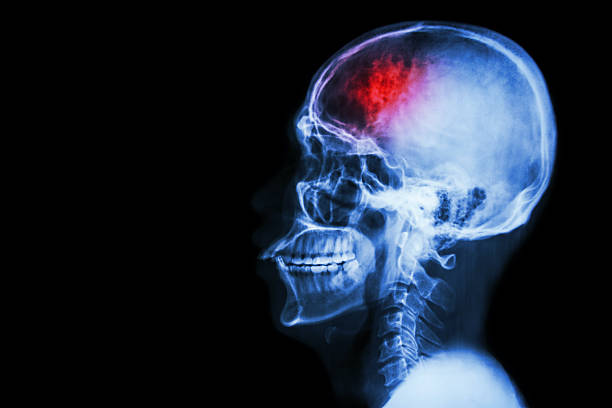

뇌출혈은 두 개 내에 출혈이 있어 생기는 모든 변화를 말하는 것으로 가장 큰 원인으로는 고혈압 증상을 지목하곤 합니다. 고혈압은 산소와 영양소가 뇌로 들어가는 통로인 혈관에서 변화를 일으키기 때문인데 뇌동맥류가 손상된 경우에도 발생할 수 있으며 잦은 흡연이나 음주 등 여러 원인으로 합병증으로 인해 발생할 수 있습니다. 특히, 뇌출혈 증상 발생시 가능한 빨리 병원으로 가야하고 약 2시간 안에 응급처치를 받아야 하는데 이는 응급처치를 받지 않으면 바로 뇌 손상으로 사망에 이를 수 있기 때문에 이번 시간에는 뇌출혈 전조증상에 대해 정리해 보겠습니다.

뇌출혈 전조증상 첫 번째는 두통입니다. 가장 흔한 뇌출혈 전조 증상은 두통이지만 두통은 누구나 경험하는 흔한 현상이기 때문에 무시되고 골든 타임을 지나게 됩니다. 뇌출혈로 인한 두통은 정상적인 두통보다 더 심할 수 있는데 이는 두통이 뇌동맥류로 인한 것이라면 많은 사람들이 일생에 최악의 두통을 경험할 정도로 심한 두통이기 때문에 빠르게 병원을 방문 해야 합니다.

뇌출혈 전조증상 두 번째는 마비입니다. 이러한 마비 증상은 한쪽에서 나타나는데 이는 우뇌는 좌측과 연결되어 있고 좌뇌는 우측과 연결되어 있기 때문에 한쪽에 유독 마비 증세가 계속 된다면 마찬가지로 뇌출혈 전조증상으로 판단해야 합니다.